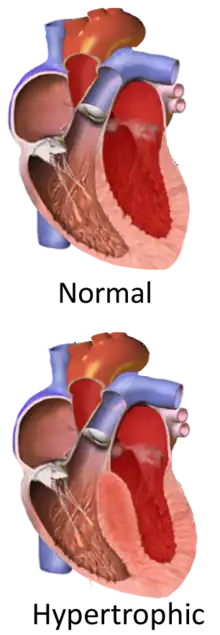

Hypertrophic cardiomyopathy (HCM, or HOCM when obstructive) is a condition in which muscle tissues of the heart become thickened without an obvious cause.[8] The parts of the heart most commonly affected are the interventricular septum and the ventricles.[10] This results in the heart being less able to pump blood effectively and also may cause electrical conduction problems.[3] Specifically, within the bundle branches that conduct impulses through the interventricular septum and into the Purkinje fibers, as these are responsible for the depolarization of contractile cells of both ventricles.[11]

Ventricular hypertrophy causes a dynamic pressure gradient across the left ventricular outflow tract (LVOT), which is associated with further narrowing of the outflow during systole. Pulling of the mitral valve leaflets towards the septum contributes to the outflow obstruction. This pulling is thought to occur by several proposed mechanisms, including that the flow of blood through the narrowed outflow tract results in it having a higher velocity, and less pressure through the Venturi effect.[19] This low pressure then causes the anterior leaflet of the mitral valve to be pulled into the outflow tract, resulting in further obstruction.[34]